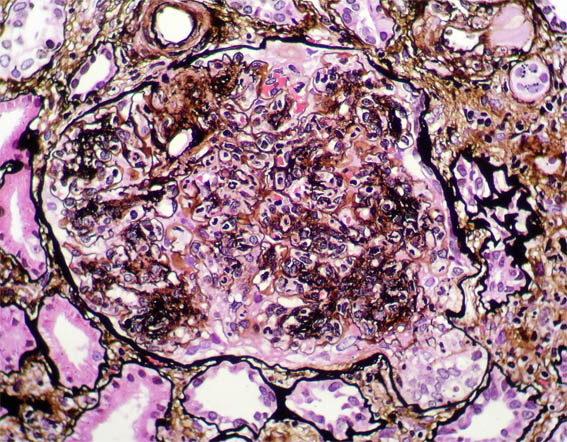

Figura 6.

Plata-metenamina, X400.